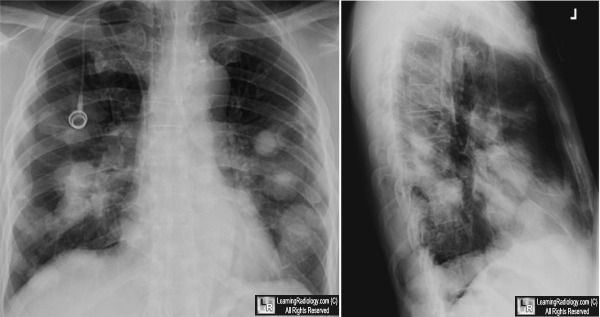

Cavitary Metastases to the Lung. Frontal and lateral chest radiograph (above) show multiple masses

in both lungs. At least one mass in the left lung (white arrow) is seen to be cavitary. An axial CT scan of the same patient demonstrates multiple masses, two of which show obvious cavitation (white arrows).